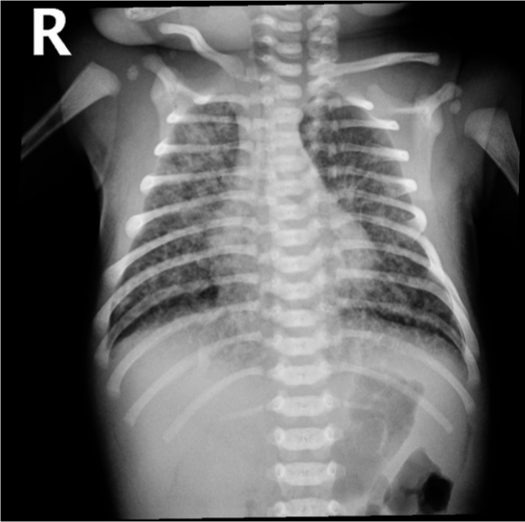

Case 2

A 39-week gestational age infant is born after prolonged rupture of membranes. The mother presented with a fever of 39°C, foul-smelling amniotic fluid, and severe abdominal pain. She was started on antibiotics shortly before delivery. The infant is born by CS due to consistent fetal tachycardia and transferred to the NICU. The infant started to have respiratory distress, apneic episodes, mild retractions, and grunting.

- What is your diagnosis? neonatal pneuomonia/sepsis?

- antibiotic, oxygen supplementation, suctioning, admission to icu, DO NOT ELECTIVELY INTUBATE

Early BPD changes in Ureaplasma urealyticum pneumonia on day 18 of life